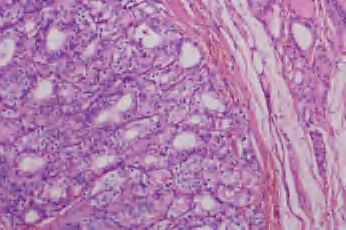

3.镜下 肿瘤细胞立方形、柱状或多角形,含一致深染的核。核分裂像罕见。继发病变包括间质水肿、纤维化、透明变性、出血、钙化,软骨化生、囊性变和梗死等(图3-31)。

图3-31 甲状腺滤泡性腺瘤